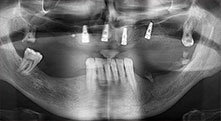

Bratu: We routinely use the instruments for harvesting bone blocks and splitting alveolar ridges. We also use the Piezomed B6/B7 for osteotomy of impacted teeth and removing failed implants. All indications that require deep, clean cuts.

Could you describe briefly, for example, your procedure for mobilizing bone blocks for transplantation?

Bratu: We prefer to harvest bone from the external oblique ridge of the posterior mandible, not from the interforaminal region. After the soft-tissue incision, we use the new saws to define the amount of bone to harvest. With this approach, we also use them for the entire preparation in almost 80% of cases. We may also use other piezo instruments and then at the end a chisel to mobilize the block. We find that this is a very effective surgical technique.